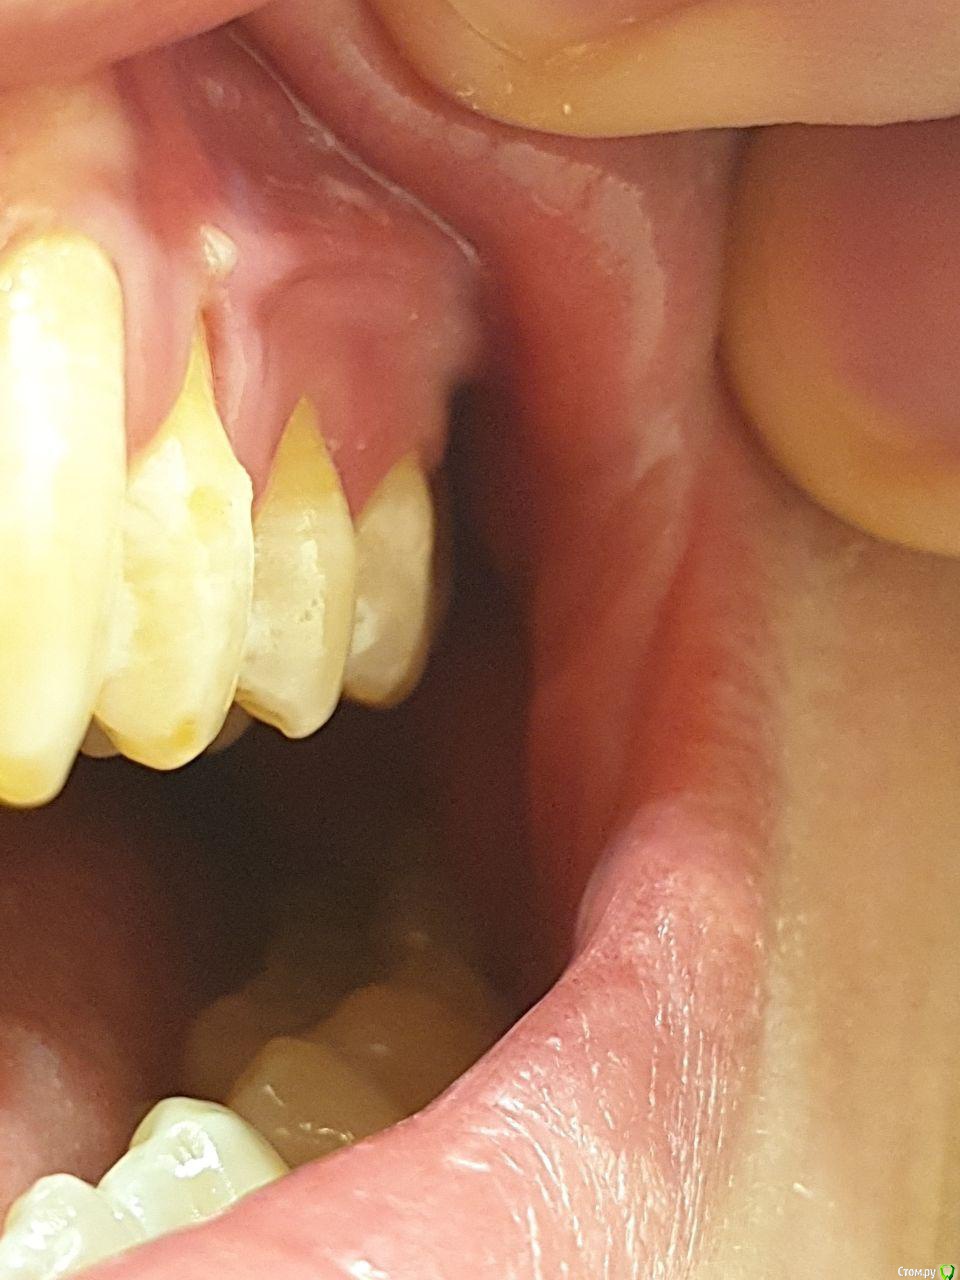

Сразу после того как выздоровел началась проблема - на 4ом зубе слева начала задираться десна. Затем со временем и на правом 4ом зубе тоже

Затем на нижней десне под центральными резцами появилась подвижная шишка, едва заметная, на фото ее не увидеть (как и почему-то не хотят видеть стоматологи, к кому я ходил). Не проходит эта шишка уже 1.5 года

Стал фиксировать убыль на фотографиях, которые приложу к данному посту. Также прикладываю результаты анализов. Помимо этого полгода назад делали панорамный снимок, который вроде как показал, что убыли костной ткани нет. На вопрос а в чем тогда проблема, мне ответили, что это просто рецессия (видимо, так задумано и все ок, пока зуб не выпадет подождем).

Добрый день. То что происходит - это рецессия десны. Десна "уползает" от коронки зуба у всех, вопрос скорости и равномерности. В вашем случае и возрасте это быстрее чем в норме.

Если будет  ползти  и дальше существуют методы хирургического добавления десны, но об этом лучше общаться с хирургами, т.к. и везде есть свои нюансы. И тогда будет нужен именно узкопрофильный специалист, который занимается десной, это делает далеко не каждый доктор..